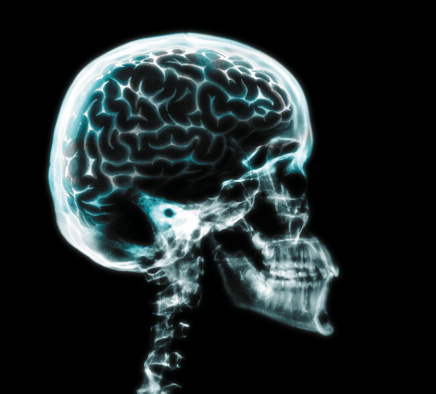

Multiple Sclerosis Month: MS Development, Multiple Sclerosis Detection, MS Treatment and Exercise

National Multiple Sclerosis Month is observed each year in March, with the aim of creating a better understanding about the neuro-degenerative disease called multiple sclerosis (MS) disease and encourage those suffering from it to make educated healthcare decisions. This month, we at Bel Marra hope to build public awareness about multiple sclerosis (MS) through articles ...click here to read more